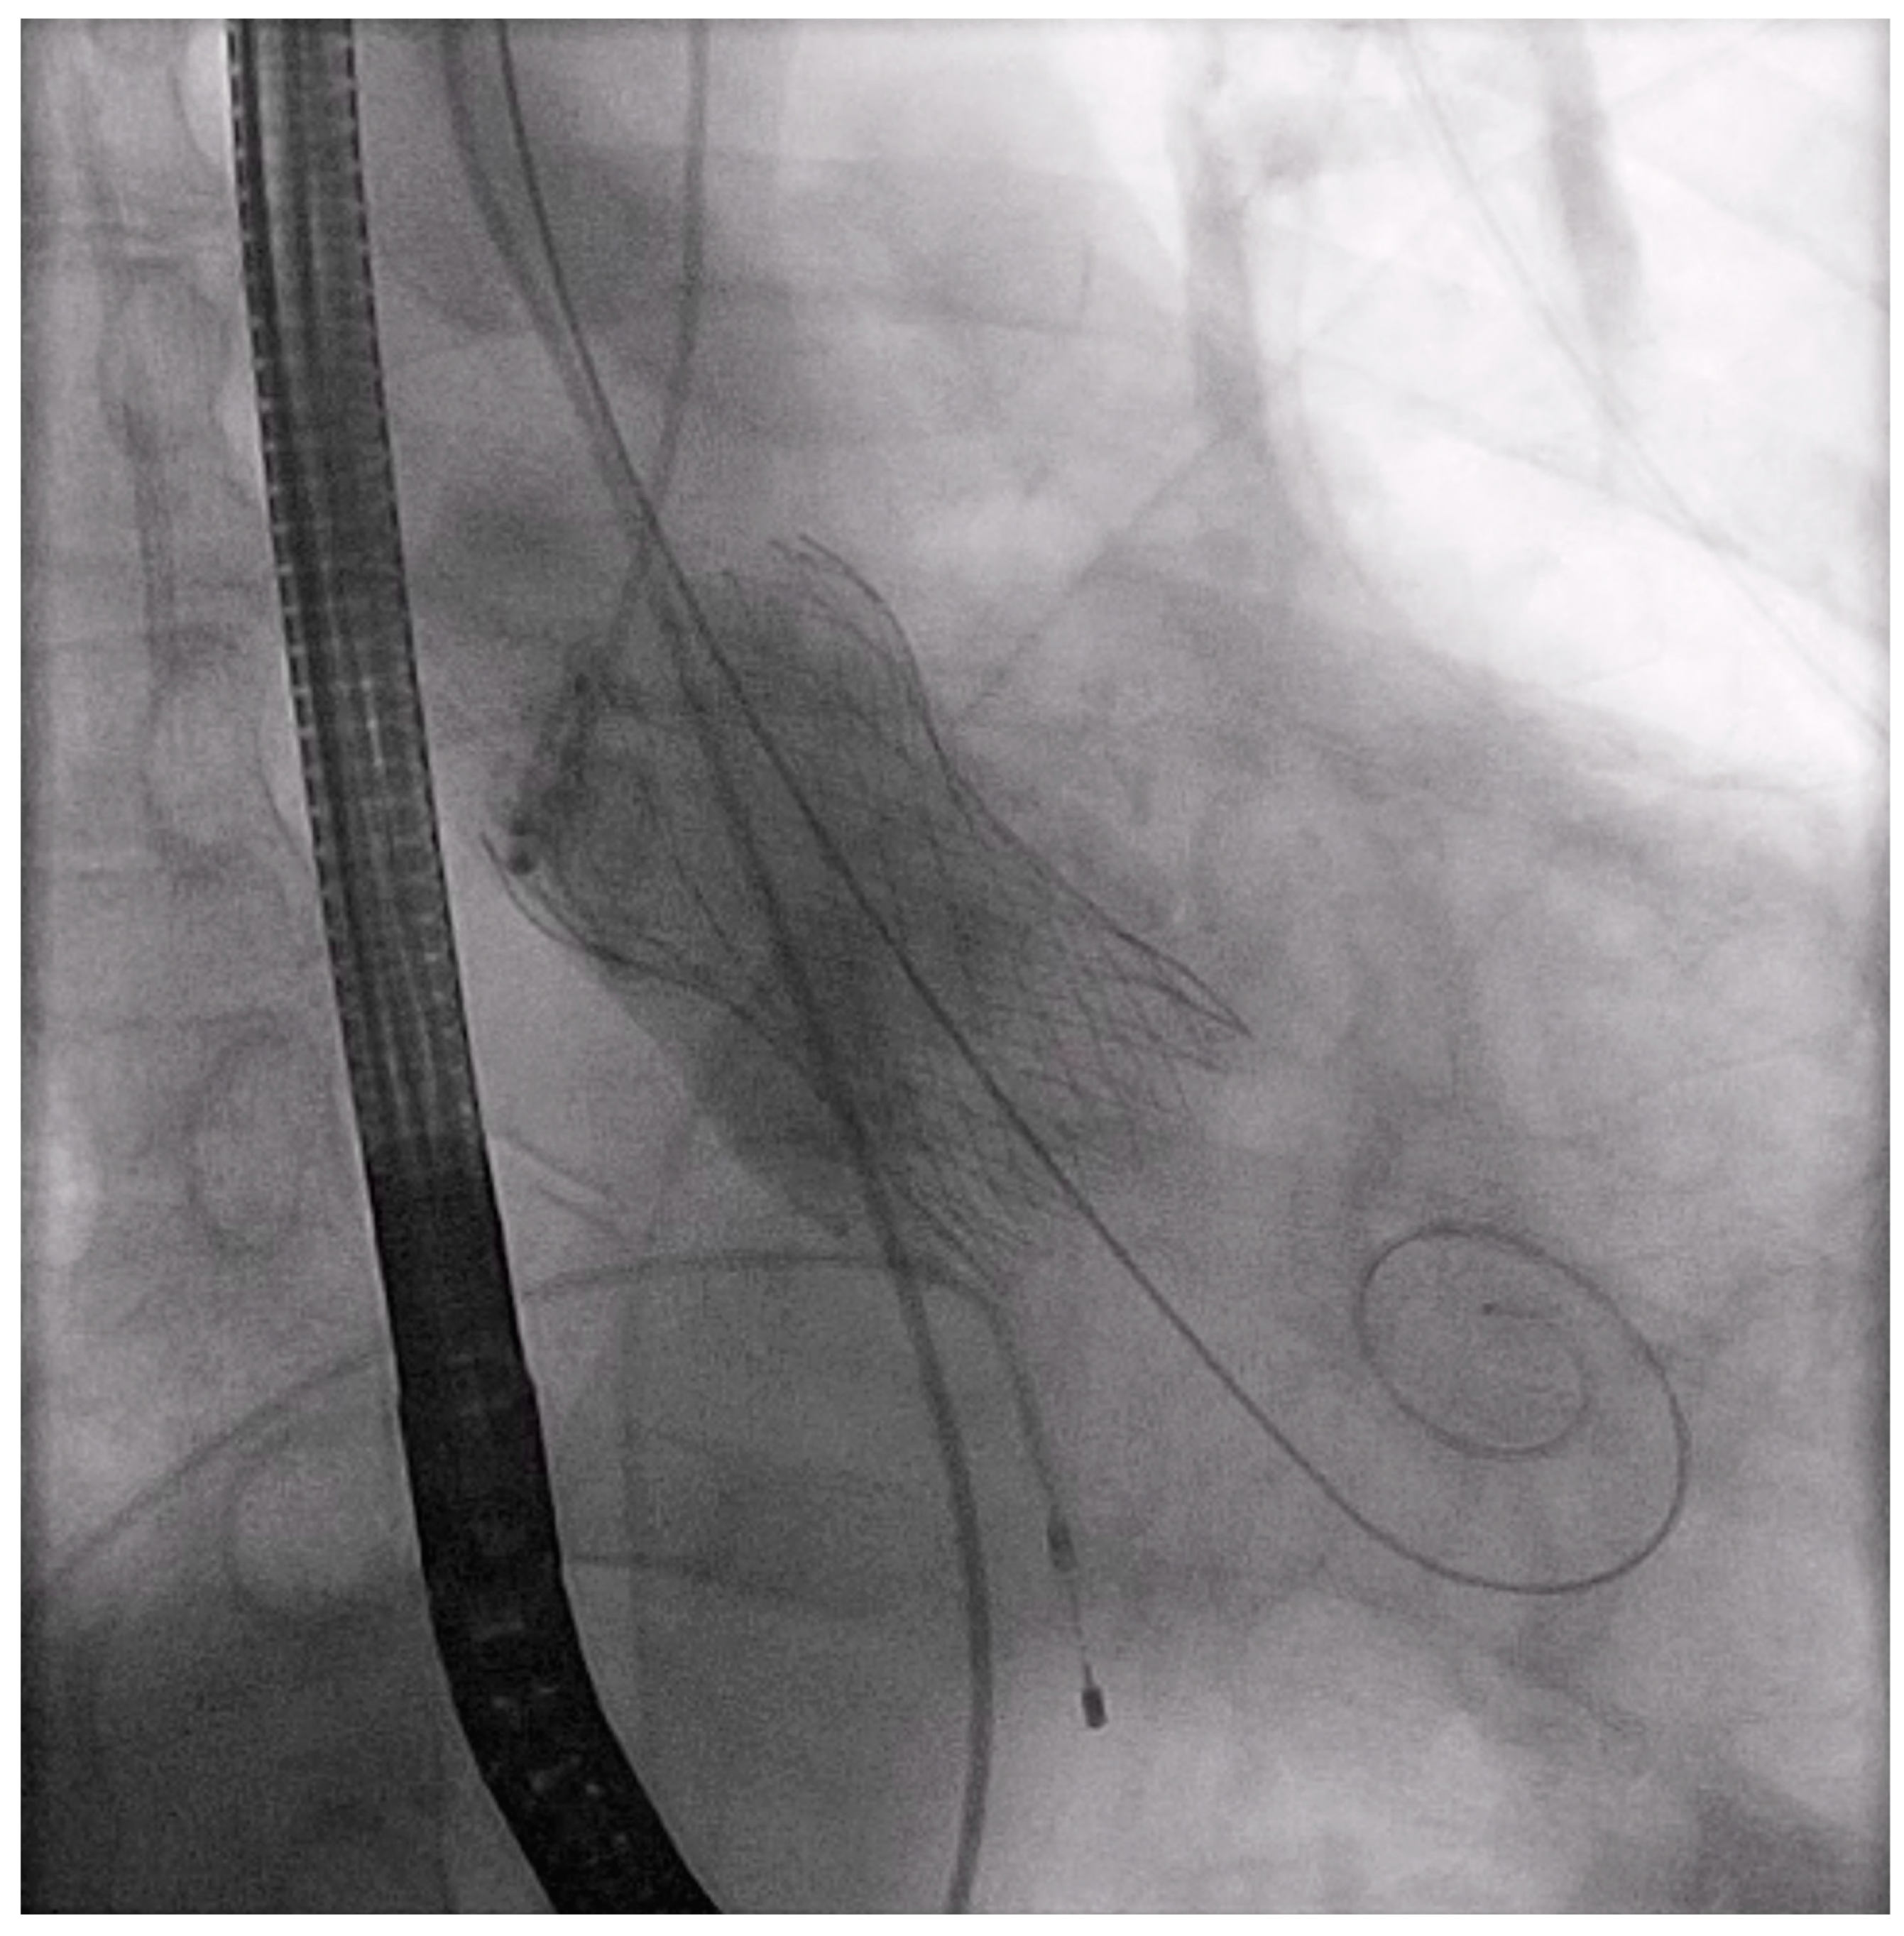

Of note, we did not continue to push the sheath to the end. From this point, the procedure followed the same technique used for the TF route. After balloon valvuloplasty (Supplementary Video S1) a Medtronic Evolut PRO+ prosthetic valve with a size of 29 mm (Medtronic, Minneapolis, MN, USA) was inserted into the ascending aorta (Supplementary Videos S2 and S3). After confirmation of the position of the Evolut valve (Supplementary Video S4), it was implanted with a pacing rate of 120/min with the cusp-overlap technique (Supplementary Video S5). There was no paravalvular or valvular regurgitation on the control aortography (Figure 4) (Supplementary Video S6).

Figure 4.

Successful implantation of Evolut valve of 29 mm.